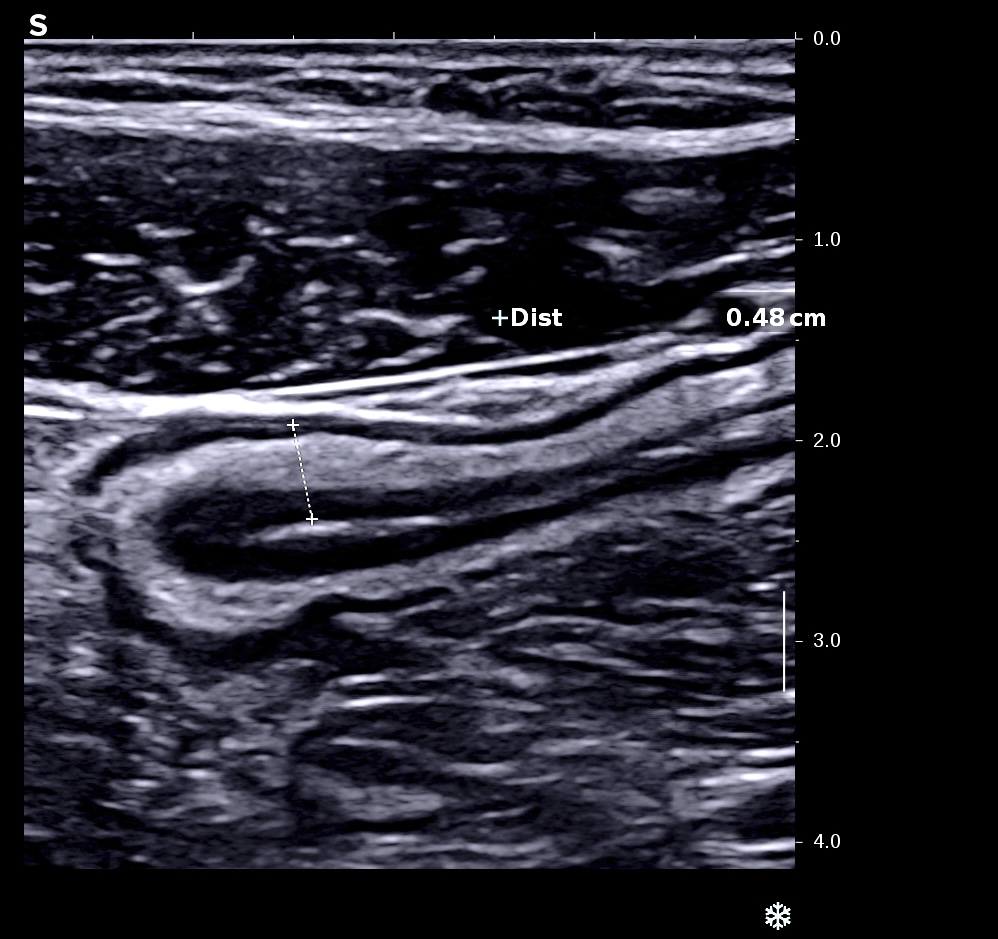

Forme plus chronique, épaississement très important de la sous muqueuse hyperéchogène par rapport à la muqueuse elle fait plus > 3/4 de la paroi

Forme chronique, aspect tubulisé du côlon, qui devient linéaire et rigide